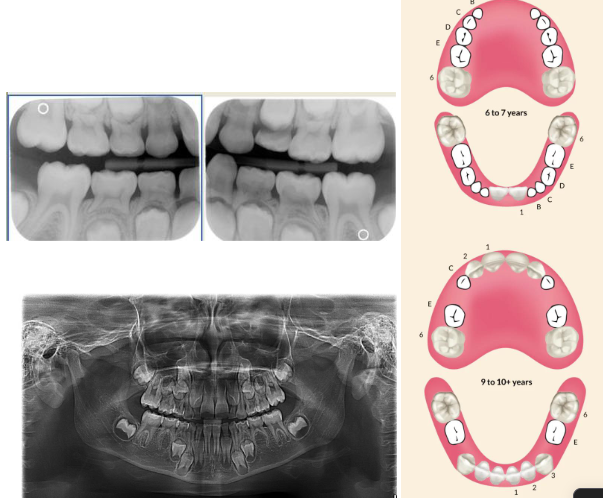

Normal eruption patterns

 As a permanent tooth develops, the root length increases and it moves into position by “pushing out” the primary tooth

 While this is happening, the primary tooth root starts to resorb and shorten

 What is happening in this radiograph?

 Primary molars

• Flared roots

• Resorption

 Permanent molars

• Straighter, longer roots

• Roots still forming

• Apical foramen open & wide

Follicular space

• RL area surrounding developing tooth

• Normal

<p><span> As a permanent tooth develops, the root length increases and it moves into position by “pushing out” the primary tooth </span></p><p><span> While this is happening, the primary tooth root starts to resorb and shorten </span></p><p><span> What is happening in this radiograph? </span></p><p><span><strong> Primary molars </strong></span></p><ul><li><p><span>Flared roots </span></p></li><li><p><span>Resorption<strong> </strong></span></p></li></ul><p><span><strong> Permanent molars </strong></span></p><ul><li><p><span>Straighter, longer roots<strong> </strong></span></p></li><li><p><span>Roots still forming </span></p></li><li><p><span>Apical foramen open &amp; wide<strong> </strong></span></p></li></ul><p><span><strong>Follicular space </strong></span></p><ul><li><p><span>RL area surrounding developing tooth </span></p></li><li><p><span>Normal<strong> </strong></span></p></li></ul><p></p>

Dental charting

knowt flashcard image